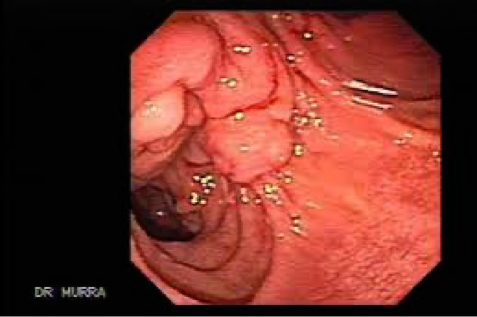

Periampullary tumor (endoscopic view)

Note: Periampullary tumors could originate from the head of the pancreas, distal CBD, or from the Ampullary mucosa of the duodenum and commonly the patient presents early with jaundice due to the early obstruction of the CBD.